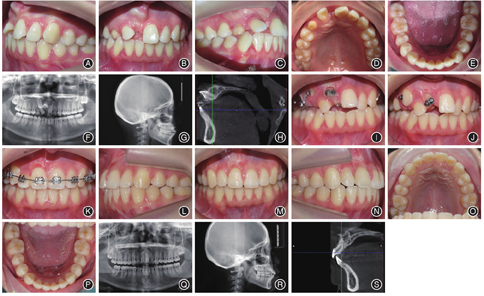

病例1女,21岁,以"自觉门牙不美观数年,要求治疗"为主诉就诊。临床检查:恒牙列,11、13缺失,53滞留,12、21轻度扭转并向缺隙处倾斜、缺牙间隙变小、上中线右偏,11近前庭沟黏膜处可触及牙齿隆起,下牙列轻度拥挤,前牙覆

覆盖正常,双侧第一磨牙中性关系。X线片及CBCT示:11为唇侧倒置埋伏牙,牙冠朝向近中、唇侧、上方,牙根朝向远中、腭侧、下方,牙冠形态正常,牙根已发育完成,根管口闭合,冠根比接近1∶1,牙根弯曲部分在根尖1/3,弯曲度约为20°。矫治过程:采用外科开窗联合正畸牵引进行治疗。采用铸造式固定矫治器加强支抗,矫治器上焊有牵引钩分别伸至11牙槽嵴顶下方及13远中,避免与对

牙有咬合干扰。由于11、13位置表浅位于黏膜下,采用开放式牵引,即局部麻醉下去除埋伏牙表面覆盖的黏膜后暴露牙冠,局部用浸有肾上腺素的棉捻充分止血,吹干,酸蚀,冲洗,吹干,隔湿,粘接舌侧扣于11冠舌侧面及13冠唇侧面,通过更换橡皮链进行间断性轻力牵引,待11牙冠唇侧暴露后,牙长轴与邻牙长轴夹角约45°时,粘接舌侧扣于11冠唇侧,增加旋转力矩,牵引力控制在60 g以下,注意牙齿位置及牵引力方向,去除牙齿

方移动的邻牙阻力。每3 ~ 4周加力1次。13个月左右11、13基本到位,牙冠暴露约1/2时粘接托槽,置推簧扩大11间隙,采用0.016澳丝+0.012 NT双丝进行初期排齐,逐渐更换弓丝序列排齐整平上下牙列,后期精细调整咬合。全口矫治时长为30个月,矫治后采用上前牙舌侧丝进行固定保持(图1)。